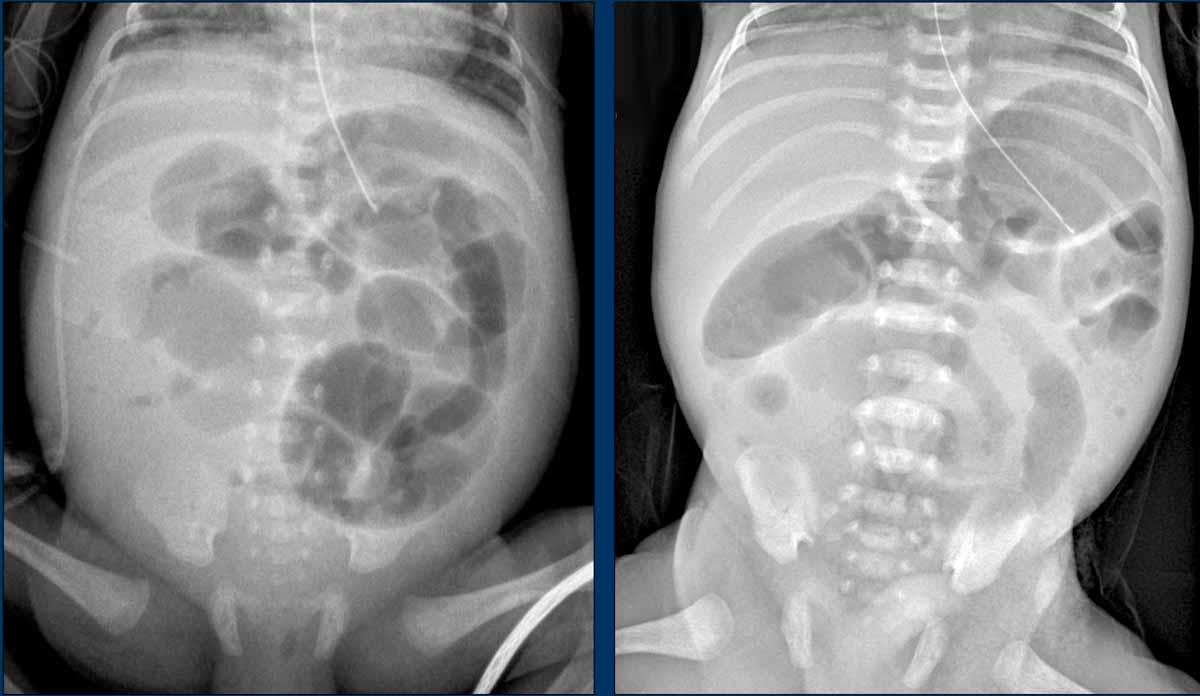

Hình ảnh

X-quang bụng cho thấy các quai ruột giãn và phân bố hơi không đều với vùng thiếu hơi ở góc phần tư dưới phải.